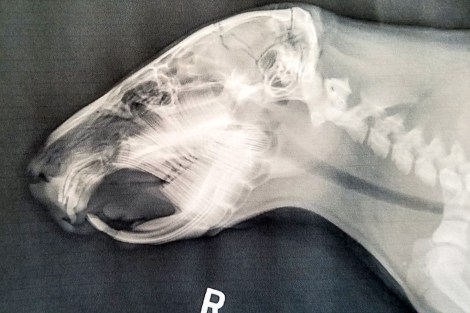

Compare Dobby’s fractured, but robust teeth with Gidget’s funky shaped teeth:

Dobby’s upper incisors show up like a uniform, solid curve. The lower incisors line up with the uppers at the cutting surface.

Gidget’s upper incisors show as a conglomerate of wiggly lines above the palate. Her lower incisors have grown too far, there being no uppers to meet and sharpen them.

Rodents have a “tooth bud” from which the tooth forms and grows. Capybaras are born with eyes open, fur, and teeth (like guinea pigs) so they are ready to graze with the herd. The teeth should grow out of the tooth bud with a uniform curve. The enamel is harder at the front (the tooth you can see), softer enamel behind (behind the tooth, in the mouth), so that the upper and lower incisors sharpen each other to razors with each bite. Gidget’s lower incisors are overgrown, but relatively normal. Her uppers look oddly misshapen, like noodles. There was no way for the upper and lowers to work together like scissors for cutting grass.